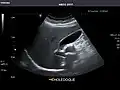

Gallbladder: No stones, wall thickening, or pericholecystic fluid.

Gallbladder -

Gallbladder